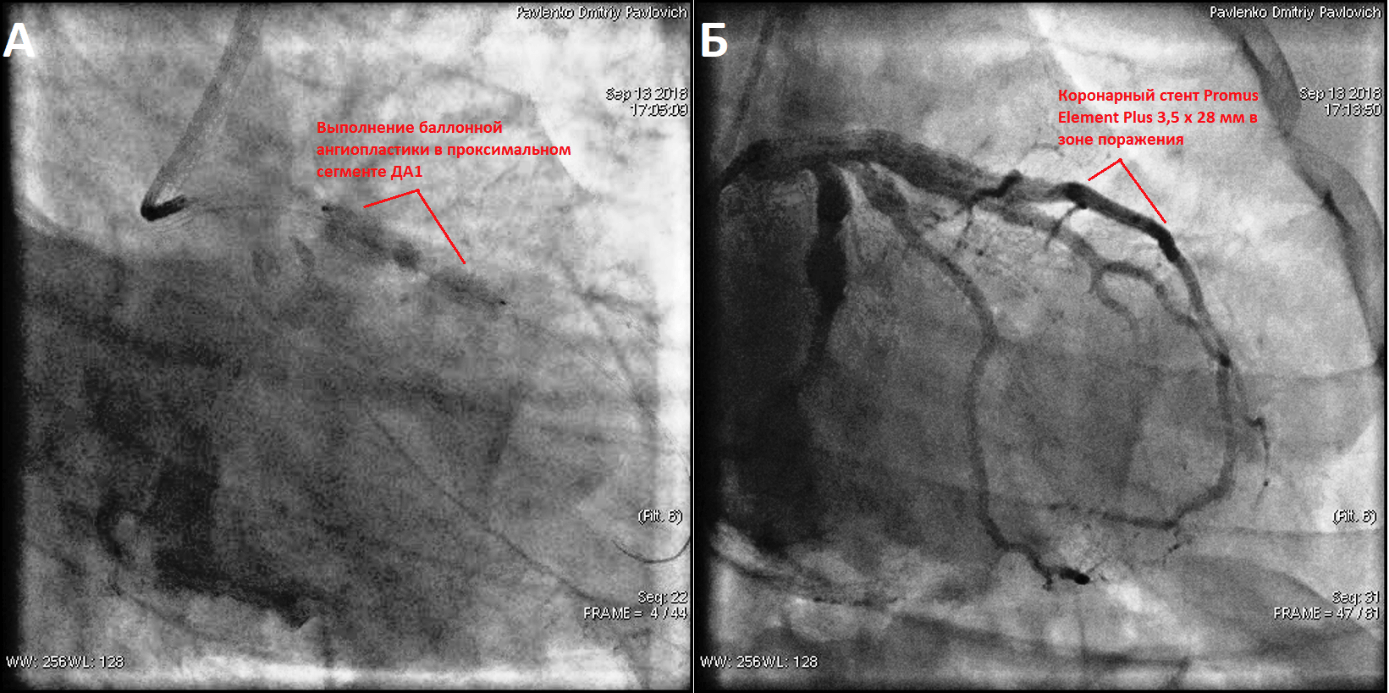

При поступлении в Военно-медицинскую академию им. С.М. Кирова при объективном обследовании, за исключением ослабления первого тона на верхушке сердца, других патологических изменений выявлено не было. Результаты клинических анализов крови и мочи были в пределах нормы. В лёгочной ткани очаговых и инфильтративных изменений не наблюдалось, корни лёгких были чёткие и структурные, синусы свободные, тень сердца не расширена. ЭКГ соответствовала переходу острейшей ЭКГ-стадии проникающего инфаркта миокарда в области передней и боковой стенок левого желудочка в острую (рис. 1). По данным биохимического исследования крови: тропонин-Т – 8,06 нг/мл, КФК – 2490 МЕ/л, КФК-МБ – 196,28 МЕ/л. При эхокардиографическом исследовании наблюдалось уплотнение стенок аорты, камеры сердца были нормальных размеров, клапанный аппарат без особенностей. Расчётное давление в лёгочной артерии в пределах нормы. На фоне сохранённой общей сократительной функции левого желудочка (60% по Simpson) были выявлены зоны акинезии в средних и верхушечных сегментах его передней и боковой стенок. На основании полученных данных был установлен диагноз: «Острый проникающий инфаркт миокарда в области передней и боковой стенок левого желудочка» и принято решение о необходимости проведения рентгенэндоваскулярной диагностики и лечения острого инфаркта миокарда (рис. 2, 3 и 4).

При коронароангиографии были выявлены множественные АКА: в проксимальном сегменте ОА, в проксимальном сегменте ПМЖВ, проксимальном сегменте промежуточной ветви ЛКА и в проксимальном сегменте ветви тупого края (ВТК). Кроме того, в устье 1 диагональной артерии (ДА), которое тоже имело небольшое аневризматическое расширение, была выявлена тромботическая окклюзия (рис. 2 и 4). Пациенту была выполнена реканализация коронарным проводником PT2 MC, который был доставлен в дистальный участок артерии. По коронарному проводнику заведен аспирационный катетер Export Advance. Выполнена тромбоаспирация с получением тромботические масс из 1 ДА и установлен стент с лекарственным покрытием Promus Element Plus 3,5×28 мм. При контрольной коронароангиографии кровоток в месте установки стента удовлетворительный (рис. 3), участков резидуального стеноза и диссекции не выявлено. На ЭКГ, зарегистрированной после чрескожного коронарного вмешательства, отмечалась ускоренная динамика проникающего инфаркта миокарда в области передней и боковой стенок левого желудочка. На фоне проводимой консервативной терапии состояние пациента улучшилось, и он был направлен на медицинскую реабилитацию в санаторий с последующим освидетельствованием для определения категории годности к военной службе.